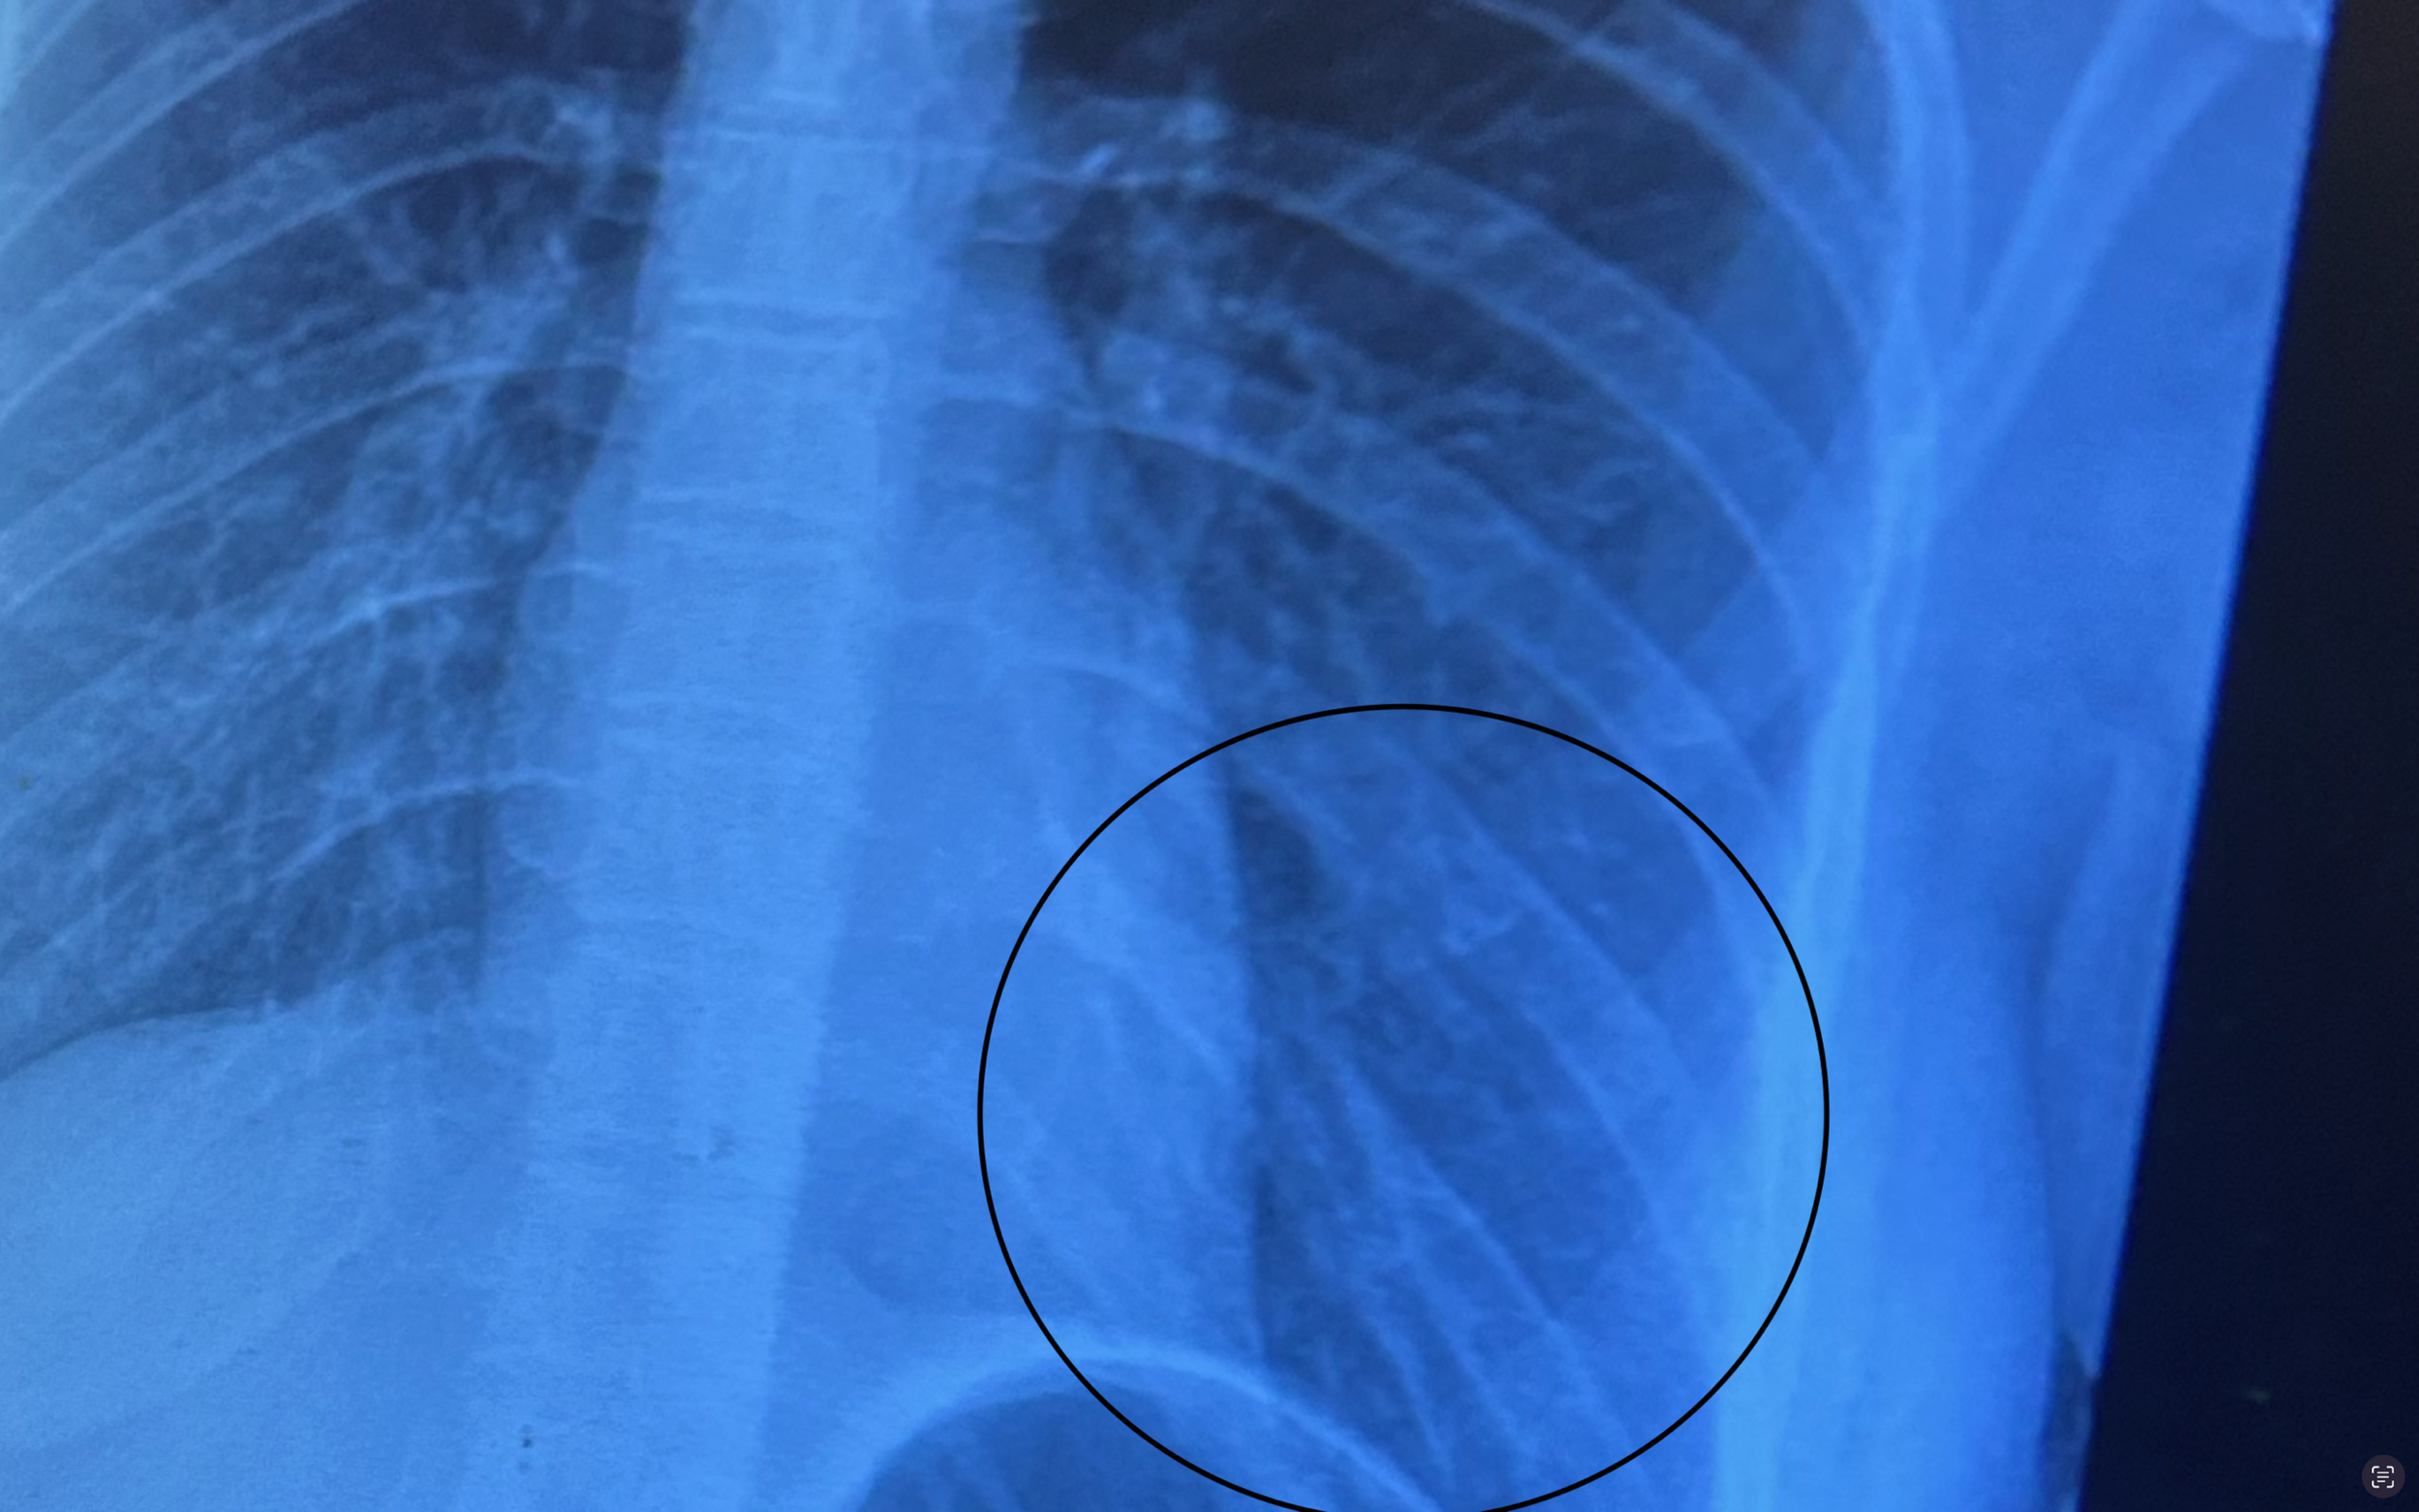

The devastation of my car was inevitable; no car could survive being flipped over like it was weightless. As for me, I was extremely lucky. I emerged from the crash with only two broken ribs.

An X-ray of the author’s ribs after a major automobile accident last fall. At the top of the page, the author’s Ford Fusion flipped when she had her Fall 2024 accident. (photos courtesy of Leanne Dudash)